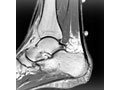

Most doctors diagnose an Achilles tendon problem by asking questions about your past health and checking the back of your leg for pain and swelling. If your symptoms are severe or don't improve with treatment, your doctor may want you to get an X-ray, an ultrasound, or an MRI.

• MRI scan. It may be used to check the tendon for signs of a tendon tear. An MRI is also used to evaluate the heel bone.